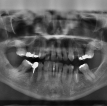

Naturalnews.com poroča: dr. Amy Hartsfield, specialistka za orofacialno bolečino in zobozdravstveno medicino v Alabami, pravi, da je v zadnjem času opazila velik porast pacientov, ki poročajo, da jih bolijo sicer zdravi zobje in čeljustne kosti in da se celo poslabša brez očitnega razloga. .

Veliko Hartsfieldovih bolnikov trpi za nevrovaskularnimi in miofascialnimi bolečinami v glavi in ​​obrazu, ki vključujejo glavobole, zobobole, ki niso povezani z dejanskim zobom ali zobmi, osteonekrozo čeljusti, težave s spanjem, tinitus ter oralne in avtoimunske bolezni obraza. Takšna stanja so povezana s težnjo cepljenja, da povzroči "mikro" krvne strdke po telesu, je pojasnil Hartsfield.

Ena takšnih oseb, ki je po injiciranju Modernine injekcije mRNA začela trpeti zaradi hude izgube kosti, je 79-letna Cheryl Alverson, ki so ji morali izpuliti vse spodnje zobe zaradi množične ponavljajoče se okužbe, ki jo je povzročila obsežna izguba kosti po injekciji.

Alverson je odšel v Hartsfield, ki je naročil več krvnih preiskav, vključno z nekaterimi, ki so bile posebej povezane s strjevanjem krvi. Pokazali so, da je Alversino telo preobremenjeno z mikrostrdki iz cepiv.

Hartsfield je ugotovil, da ti mikrostrdki neposredno motijo ​​​​celjenje kosti po ekstrakciji, da ne omenjamo dejstva, da se običajno pojavijo samo pri bolnikih, ki jemljejo zdravila za osteoporozo ali so bili podvrženi radioterapiji, pri čemer v Alversonovem primeru nobena od teh metod ni bila uporabljena.